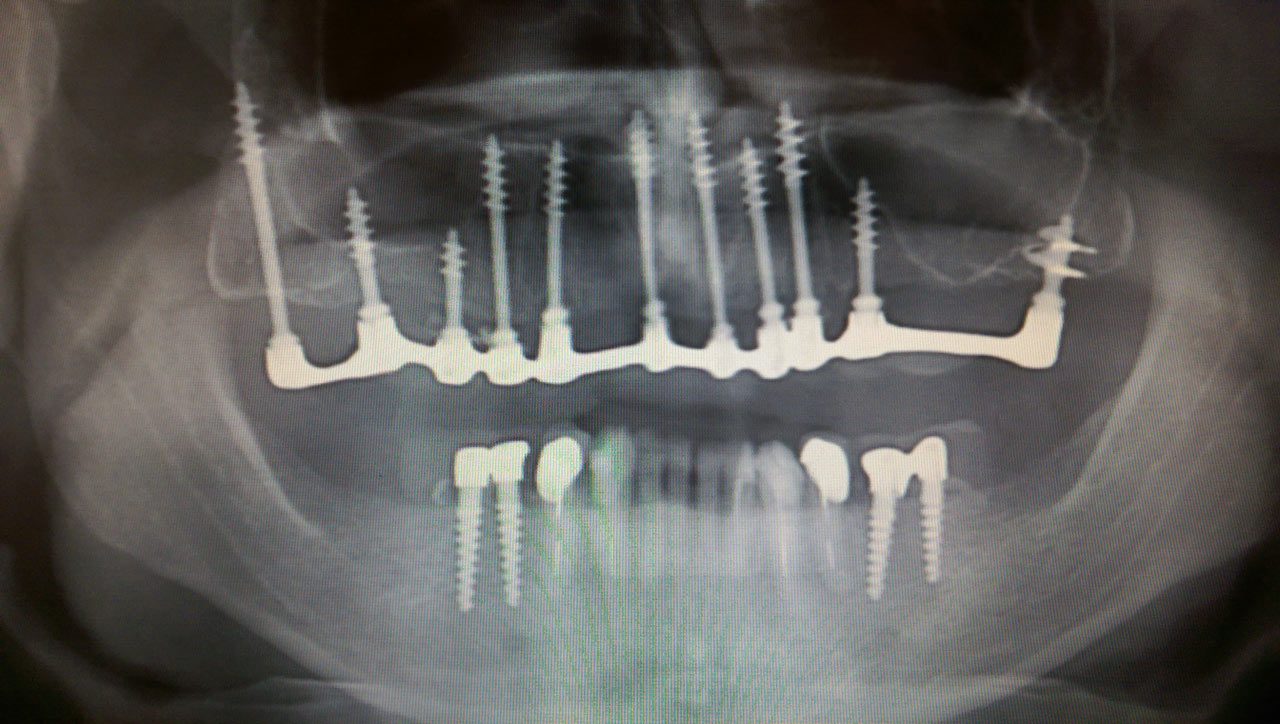

Teljes szájüregi rehabilitáció két lépésben

Ismét egy teljes szájüregi rehabilitáció két lépésben. Először az alsó fogak lettek kihúzva és azonnal implantálva, híddal ellátva, majd később a felső. IHDE svájci azonnal terhelhető implantátumok és cirkónium hidak. Dr. Kelemen Péter és a Symbion Fogtechnika közös munkája.